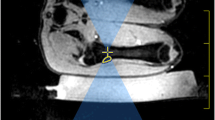

Experiments were performed in ex-vivo lamb legs (n = 8) obtained from a butcher. These were available at a uniform weight of approximately 2 kg, with the skin and subcutaneous fat mostly removed. A 3T Achieva MR/Sonalleve HIFU system (Philips Healthcare, Best, The Netherlands/Vantaa, Finland) was used. Experiments were performed at room temperature (19–22 °C) rather than a physiological temperature. Lamb leg samples were removed from refrigeration at least 12 h before experiments and placed in the scan room to equilibrate to room temperature for at least 4 h. Prior to ultrasound exposure, MR-SPOT markers (Beekley Medical, Bristol, CT, USA) were inserted into the uppermost surface of the lamb legs to act as spatial reference markers. Samples were then positioned in direct acoustic contact with a de-gassed water-dampened Aquaflex gelpad (Parker Laboratories Inc., Fairfield, NJ, USA) placed over the acoustically transparent membrane that covers the Sonalleve transducer (Fig. 1).

A lamb leg sample shown mounted for sonication in close acoustic contact with a dampened Aquaflex gelpad. The gelpad was acoustically coupled to the membrane covering the high-intensity focused ultrasound (HIFU) window coil using de-gassed water. The mobile, 256-element, 14 cm radius-of-curvature, phased-array ultrasound equipment is located beneath this membrane. The lamb leg sample was secured in place using the HIFU pelvis coil. The pelvis and window coil were operated in dual coil mode for imaging

Imaging experiments

ADC maps were calculated only for b-values of 100 and 700 s/mm2; b = 0 s/mm2 data were excluded. The DWI slice position coinciding with each planned treatment cell was identified. Regions of interest (ROIs) were then drawn on the relevant slice of the ADC maps to encompass the heated regions seen on PRFS thermometry (Fig. 2) and were subsequently copied to the equivalent regions on ADC maps generated at each time point, including the repeat baseline acquisitions. The mean ADC values for the ROIs drawn for each cell size at a range of sonication powers at each time point were plotted as time intensity series and compared. Time after sonication was calculated as the time interval between the end of sonication and the start of DWI acquisition. To determine whether any ADC changes were seen in muscle tissues outside the heated focal regions, an additional control ROI was drawn at the distal cortical surface and ADC values recorded at every time point for the two highest power exposures at each cell size.

a T1-weighted image showing a lamb leg sample placed on a gelpad for sonication, with the heated region indicated by a colour overlay of the temperature map derived from PRFS (red pixels > ~60 °C). The sonicated cell (yellow ellipsoid) is shown magnified for greater clarity in (b), with the heated region shown in units of thermal dose (red pixels > ~400 equivalent minutes (EM)). The white line indicates the 240 EM at 43 °C thermal dose contour. ROI positions representing the heated region on the relevant slice of the ADC map (green outline), and a control region placed distally (red outline) are shown in (c)